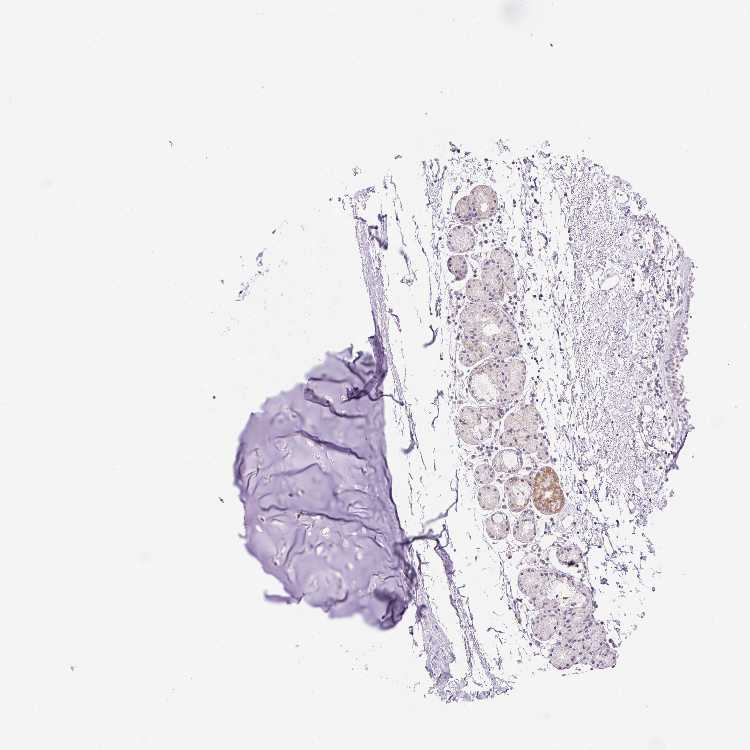

SOFT TISSUE 1 - Antibody stainingi

Antibody staining in the annotated cell types in the current human tissue is reported as not detected, low, medium, or high, based on conventional immunohistochemistry profiling in selected tissues. This score is based on the combination of the staining intensity and fraction of stained cells.

Each image is clickable and will lead to virtual microscopy that enables deeper exploration of all samples and also displays staining intensity scores, fraction scores and subcellular localization as well as patient and tissue information for each sample.

Antibody HPA051063

Chondrocytes Not detected

Fibroblasts Not detected

Peripheral nerve Not detected

SOFT TISSUE 2 - Antibody stainingi